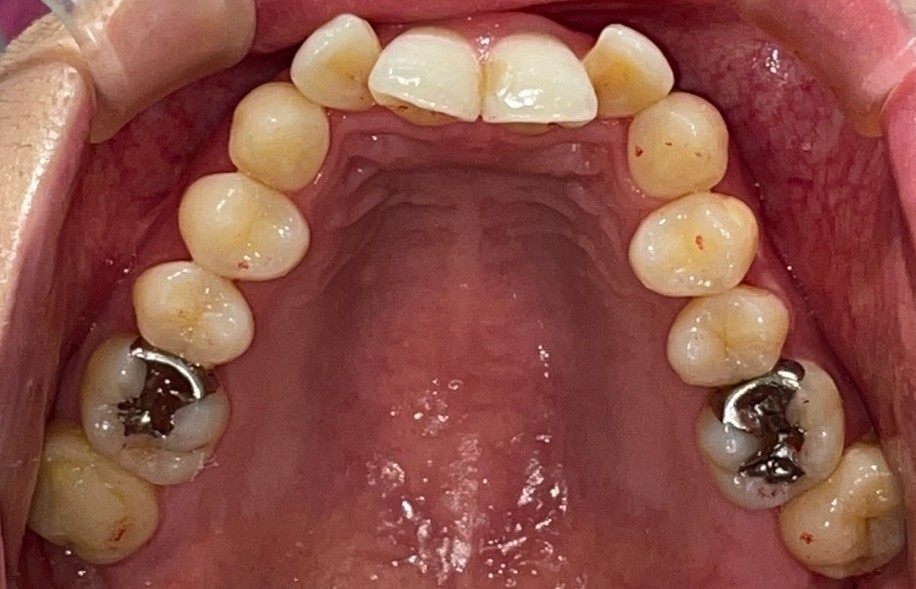

Before

After

矯正の種類 / invisalign GO

年齢・性別 / 40代女性

主訴  /  叢生

治療期間 / 12ヶ月

費用 / 簡易検査 5,000円(税別) 精密検査 30,000円(税別)

両額マウスピース 450,000円(税別)  両額リテイナー料 60,000円(税別)

※マウスピース交換時別途調節料3,000円(税別)

副作用 / 口内炎・歯の移動に伴う痛み・知覚過敏 ※数日で収まる場合が多いです

リスク / 後戻り防止の為、夜のみマウスピースで保定を指示